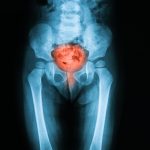

What is an enlarged bladder? Causes and symptoms

An enlarged bladder is a medical condition where the sac involved in holding urine becomes larger than normal. It is referred to in the medical community as bladder hypertrophy. The condition is characterized by thicker bladder walls that become larger from overstretching.

An enlarged urinary bladder may occur from birth, while other enlarged bladder causes are the result of an obstruction of some sort, most likely post-renal or in the bladder itself. This leads to an abnormally high volume of urine in the bladder that fails to empty as it normally would. Continue reading…